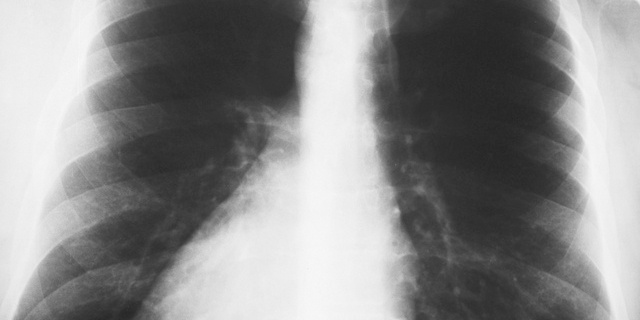

軽度と診断されれば外来治療を中心に行い、重度であれば入院となりますが、かなり重症の場合は、ICUでの入院治療を行う場合もあります。 気管支炎と肺炎を併発した場合の検査

□ 血圧検査

□ 体温などのバイタルノチェック

□ 胸部X線検査

□ 血液検査

□ 迅速検査

□ 喀痰のグラム染色検査

□ 喀痰や血液の培養による原因菌の検査など 気管支炎と肺炎を併発した場合の治療内容